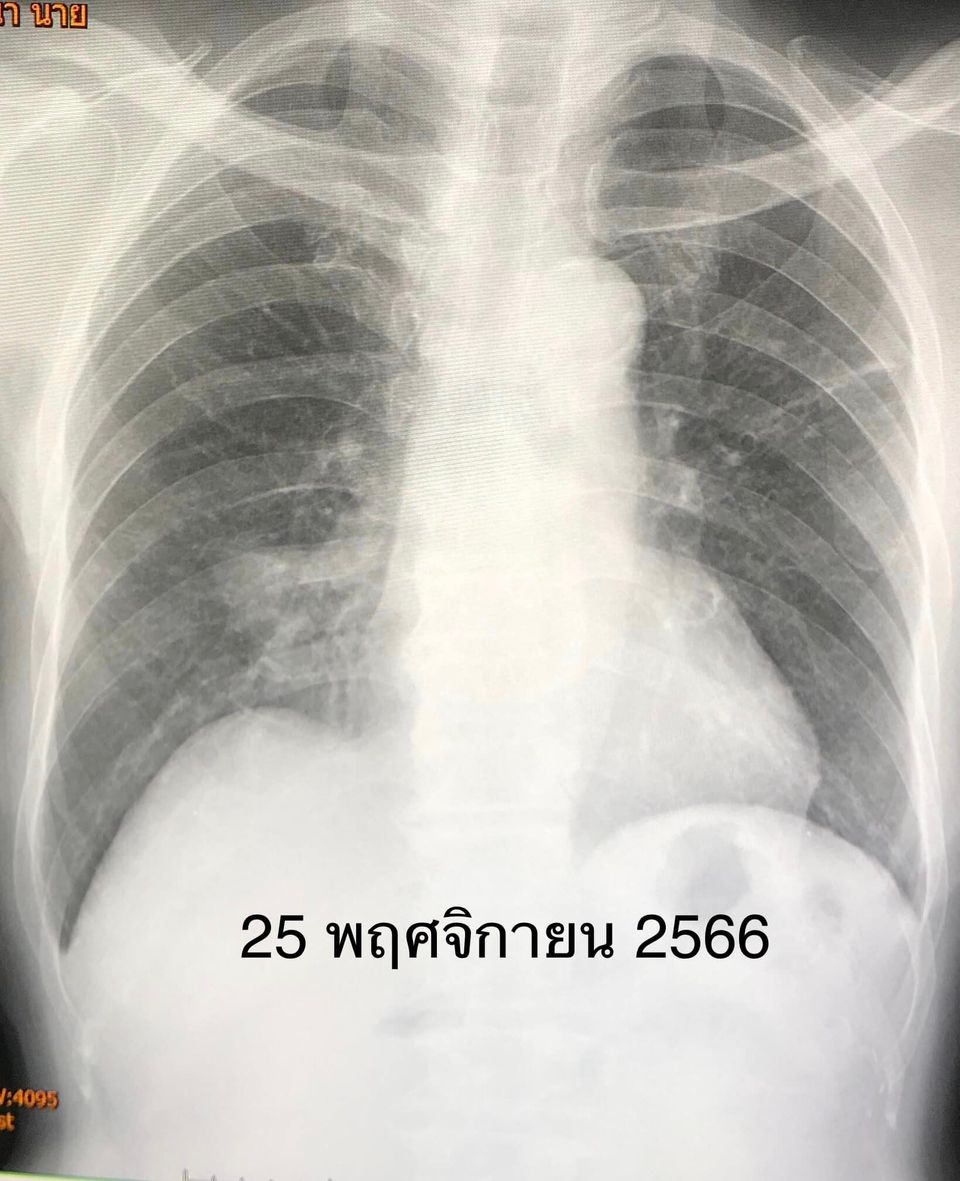

เคสนี้แพทย์รักษาด้วยการให้กินยาวัณโรคไอโซไนอะซิด พัยราซินาไมด์ อีแธมบูทอล และมอกซิฟลอกซาซิน ต่อเนื่อง 1 ปี ไม่ไอ มีความอยากอาหาร น้ำหนักขึ้น 14 กิโลกรัม ผลเอกซเรย์ปอดดีขึ้นมาก หลังหยุดกินยา 4 ปี วัณโรคไม่กลับมาใหม่ เอกซเรย์ปอดยังมีร่องรอยวัณโรคเก่าบ้าง